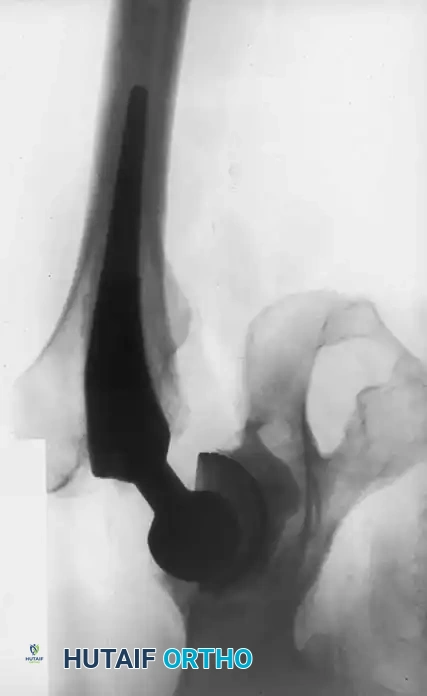

The Extended Trochanteric Osteotomy (ETO)

For complex femoral revisions, particularly those involving well-fixed cementless stems, varus remodeling, or extensive distal cement mantles, the Extended Trochanteric Osteotomy (ETO) is the gold standard.

Biomechanics of the ETO:

Unlike a standard trochanteric osteotomy, the ETO preserves the insertion of the gluteus medius and minimus proximally, and the origin of the vastus lateralis distally. This maintains a continuous myofascial sleeve, providing dynamic stability to the osteotomy fragment and dramatically improving union rates (typically >95%).

ETO Technique:

1. Measure the required length of the osteotomy preoperatively (usually 12-15 cm, ensuring it bypasses the well-fixed portion of the stem).

2. Elevate the vastus lateralis anteriorly to expose the lateral femur.

3. Use an oscillating saw or high-speed burr to make the posterior and anterior longitudinal cuts.

4. Complete the distal transverse cut, ensuring rounded corners to prevent stress risers.

5. Lever the fragment open anteriorly, hinging on the intact anterior periosteum and vastus lateralis.